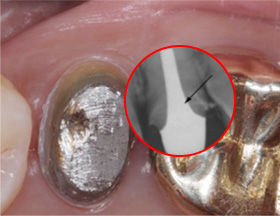

치근단 부위 회복

염증을 제거하는 신경치료 후 치근단 부위가 빠르게 회복되어 깔끔하게 신경치료를 완료하고 크라운 보철물을 씌웠습니다.

치근단 염증

캐스팅 포스트 제작

캐스팅 포스트

크라운치료